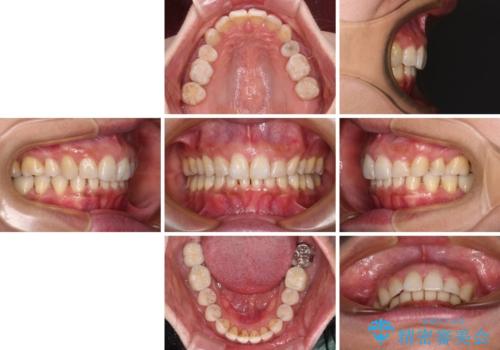

- 以前行った抜歯矯正が後戻りし、開いてしまったスペースが気になるとのことで来院された患者様です。

インビザラインを用いて開いてしまったスペースと前歯のデコボコを改善することとしました。

矯正治療後には気になっていた銀歯をセラミッククラウンやセラミックインレーにて治療することとしました。

上顎前歯を左右対称となるように歯列を整えたいとのことでしたが、すり減って形態が大きく異なっていたため、できる範囲での仕上がりとなりました。